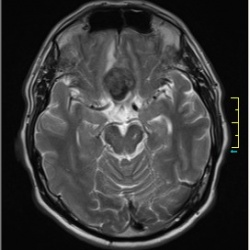

Только что сделано. Вот пример другой гидроцефалии, опухолью сдавлен и ствол и цистерна и границы ретроцелебеллярной кисты видим чётко и ясно, что полость замкнута, и ликвор в опухоли видим и...